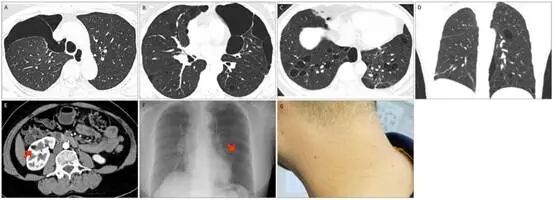

图片

图5 BHDS患者的肺部、肾脏和皮肤表现。(A-D)三名不同 BHDS 患者的肺部 CT 图像显示囊性病变。(E)腹部冠状 CT 重建显示一名 BHDS 患者的肾血管平滑肌脂肪瘤(箭头所示)。(F)胸部 X 线片(DR)显示一名 BHDS 患者的右侧气胸(箭头所示)。(G)一名 BHDS 患者颈部有多个小米粒大小的肉色丘疹(纤维毛囊瘤)。